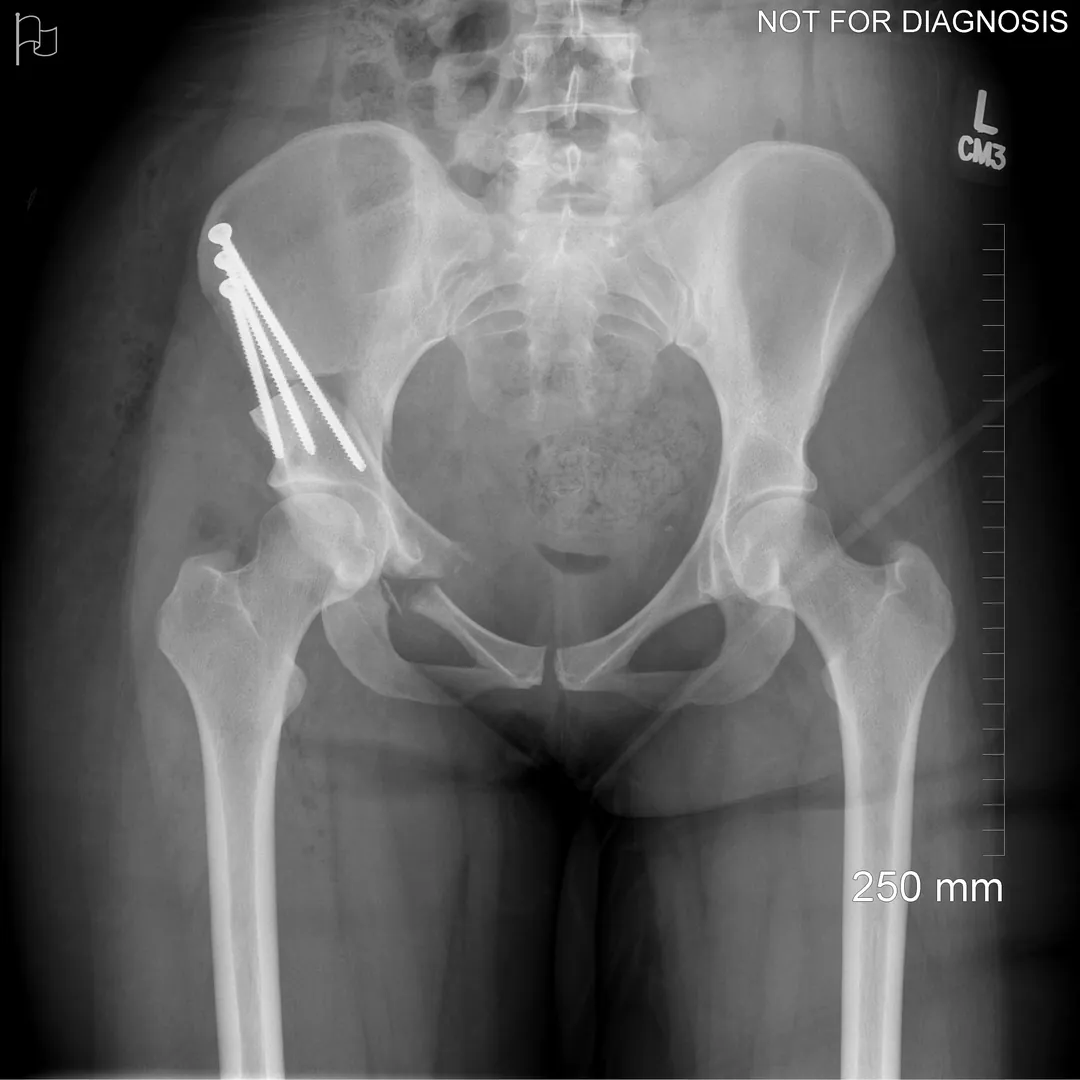

During a PAO, the surgeon carefully cuts the bone around the hip socket and repositions it to provide better coverage of the femoral head. The socket is then fixed in its new position using screws. The goal is to improve hip stability, reduce pain, and preserve the patient’s natural hip joint.

Diagram 3: Hip After Periacetabular Osteotomy (PAO)

• Acetabulum repositioned to improve femoral head coverage

• Load more evenly distributed across the joint

• Screws shown securing the acetabulum in its new position

These diagrams are commonly used in clinic to help patients visualize the problem and understand how PAO corrects hip mechanics. Dr Grammatopoulos will review your X-rays alongside these illustrations to explain your individual anatomy and surgical plan.